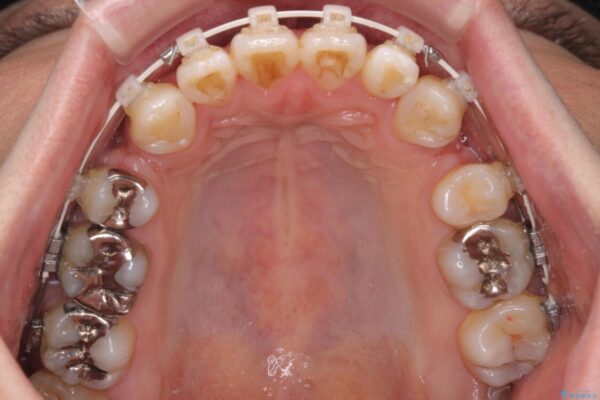

治療前

• 口元の突出感を改善!目立ちにくいワイヤー矯正で自信を持てる自然な横顔に 治療前画像

精密検査の結果、上下左右の小臼歯4本を抜歯し、そのスペースに前歯を後方へ移動させる矯正治療をご提案しました。

装置は、透明感のあるクリアブラケットとホワイトコーティングされたワイヤーを使用した、目立ちにくい審美装置を選択。